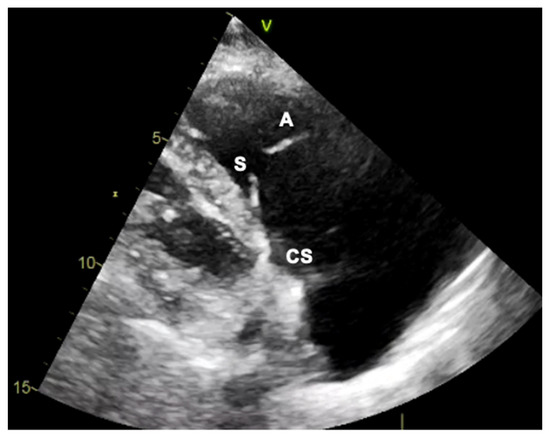

3.2. Intracardiac Echocardiography: Strenghts and Limitations

3.3. Fluoroscopy